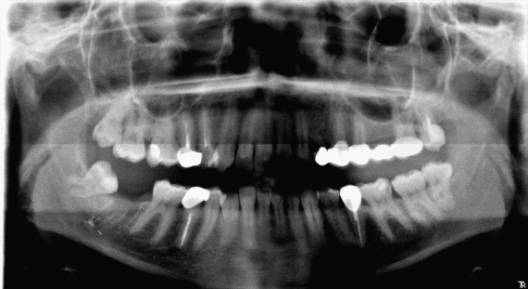

На ОРТПГ и RVG, в области отсутствующего 47зуба, наблюдается инородное тело, рентгеноконтрастное, с чёткими границами, неопределённой формы, размером 0,5/0,5 см (предположительно пломбировочный материал), находящееся в проекции нижнечелюстного канала, в области верхушки дистального корня, раннее удалённого 47зуба.